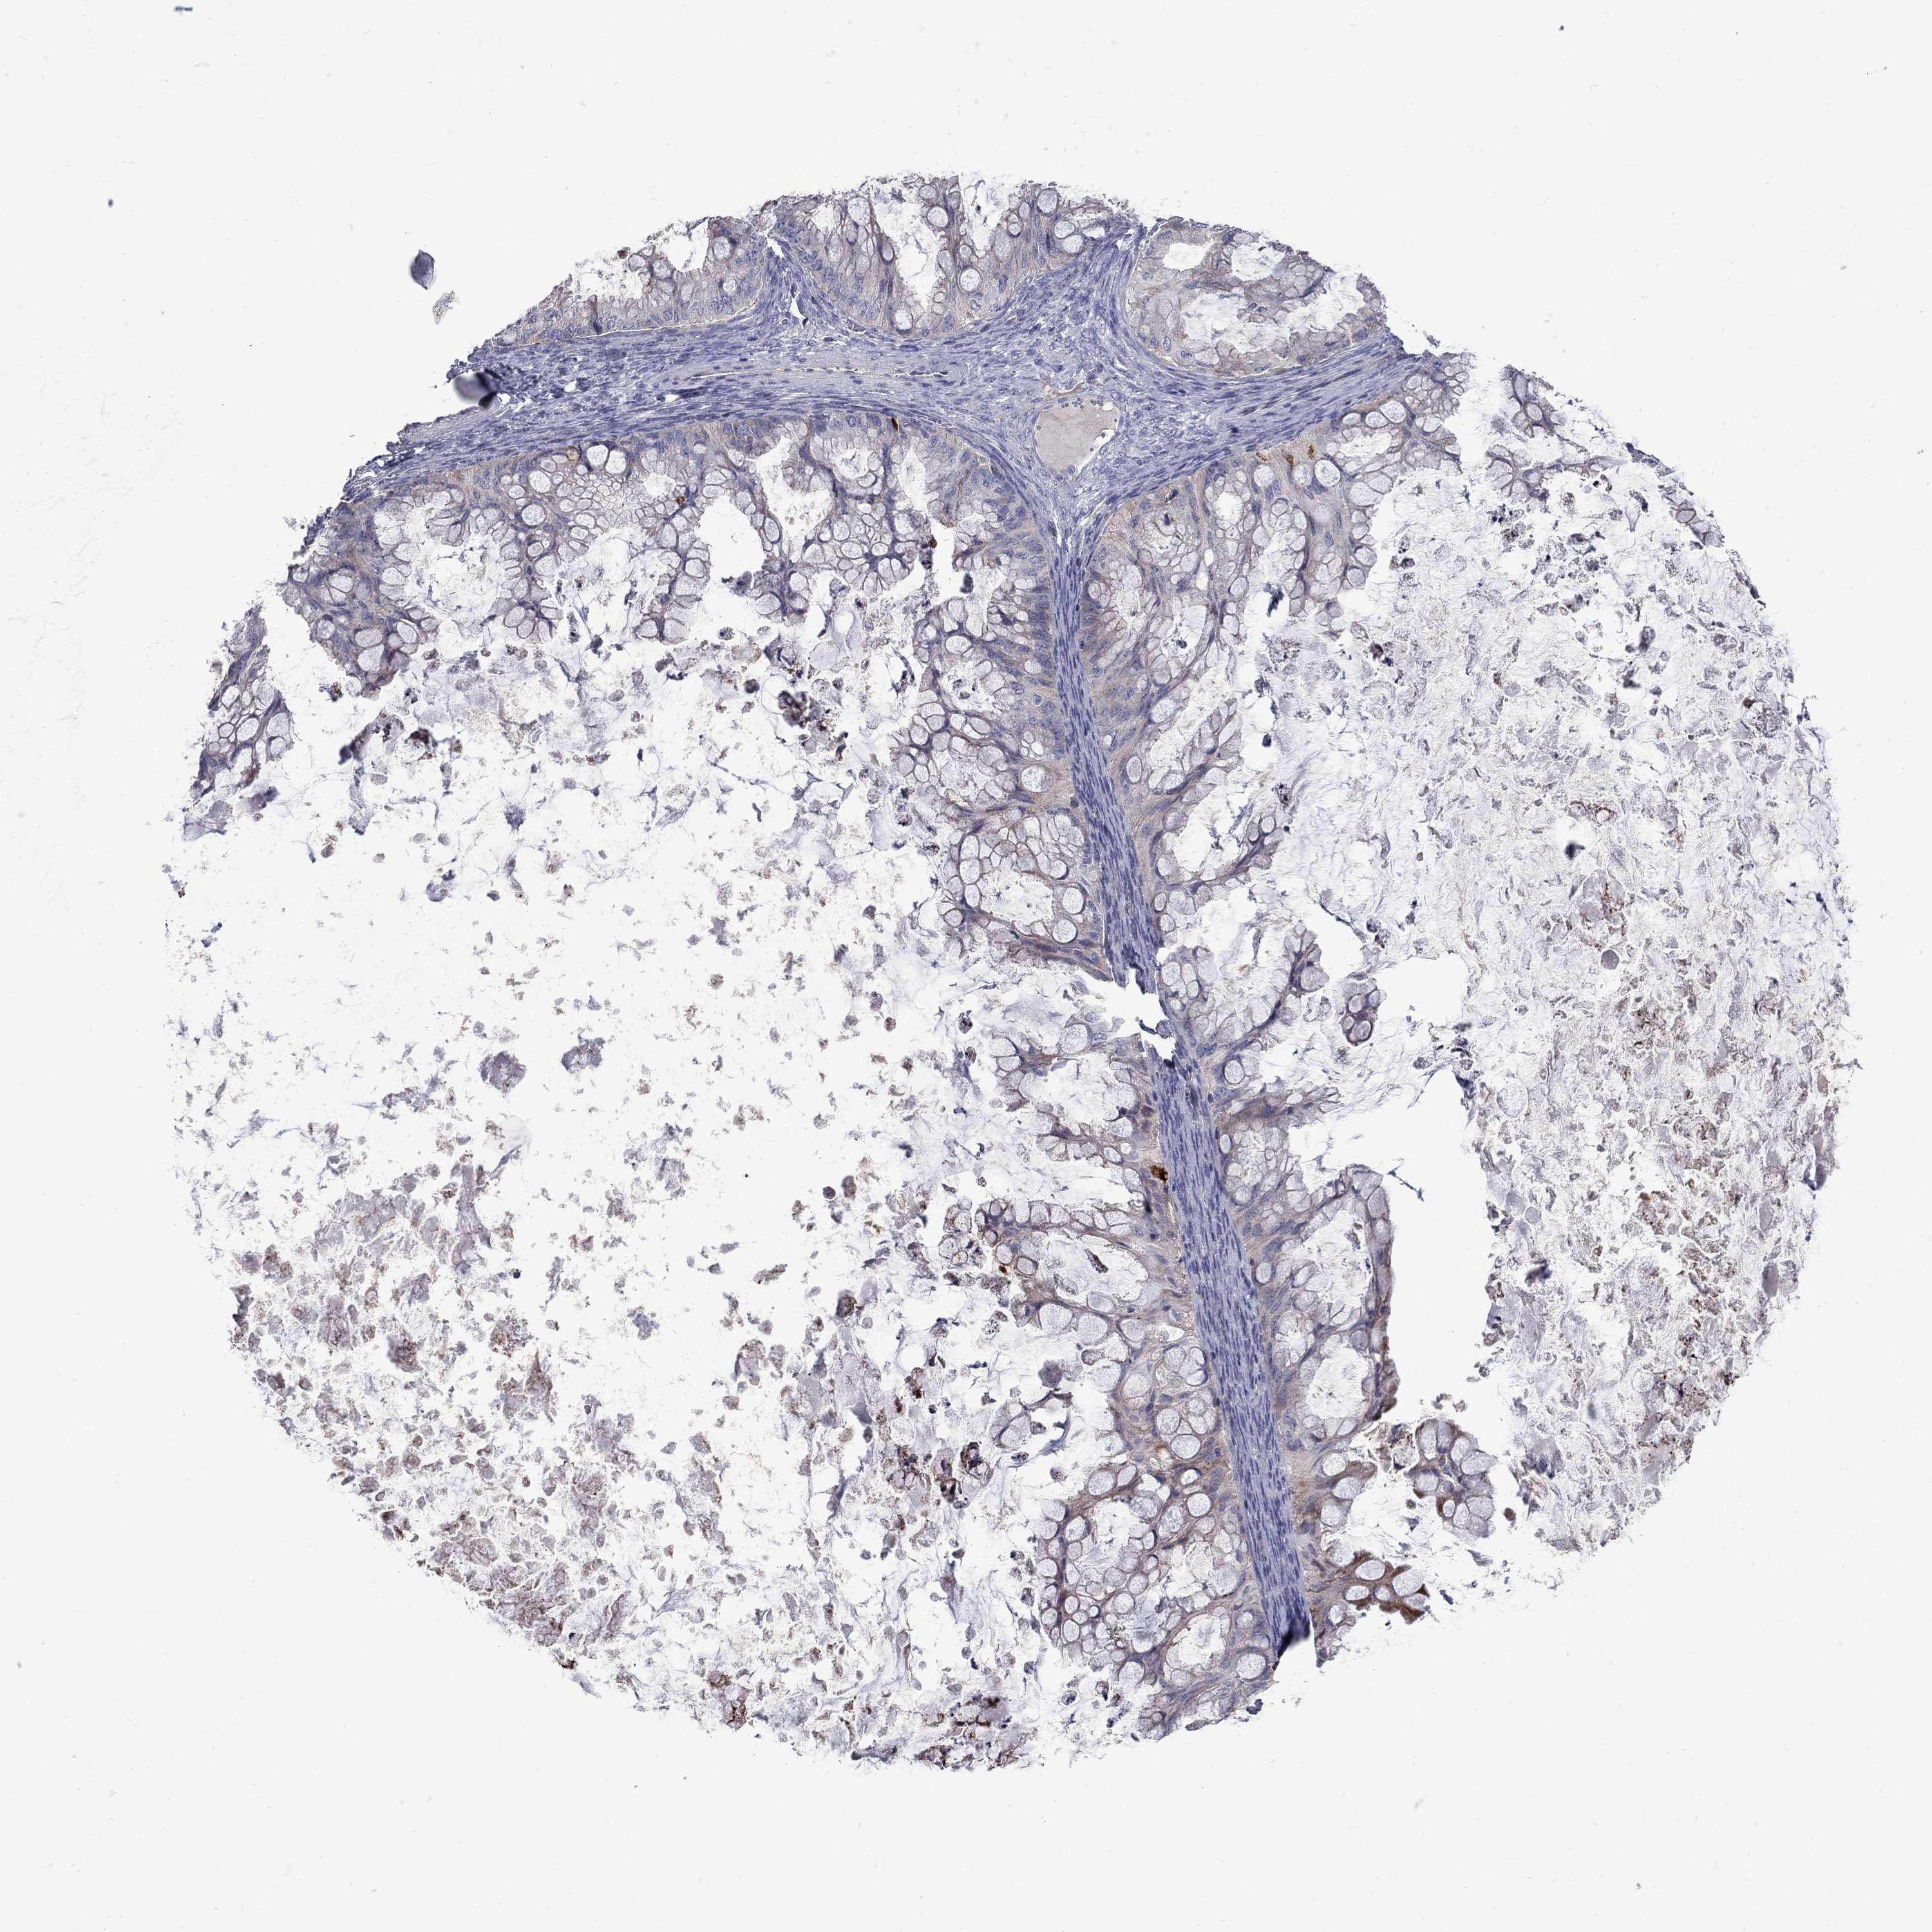

OVARIAN CANCER - Protein expressioni

A mouse-over function shows sample information and annotation data. Click on an image to view it in a full screen mode. Samples can be filtered based on level of antibody staining by selecting one or several of the following categories: high, medium, low and not detected. The assay and annotation is described here.

Note that samples used for immunohistochemistry by the Human Protein Atlas do not correspond to samples in the TCGA dataset.

Antibody stainingi

Antibody staining in the annotated cell types in the current human tissue is reported as not detected, low, medium, or high, based on conventional immunohistochemistry profiling in selected tissues. This score is based on the combination of the staining intensity and fraction of stained cells.

Each image is clickable and will lead to virtual microscopy that enables deeper exploration of all samples and also displays staining intensity scores, fraction scores and subcellular localization as well as patient and tissue information for each sample.

Antibody HPA076875

Staining

High

Medium

Low

Not detected

Intensity

Strong

Moderate

Weak

Negative

Quantity

>75%

75%-25%

<25%

None

Location

Nuclear

Cytoplasmic/membranous

Cytoplasmic/membranous,nuclear

Cystadenocarcinoma, serous, NOS

Cystadenocarcinoma, mucinous, NOS

Carcinoma, endometroid